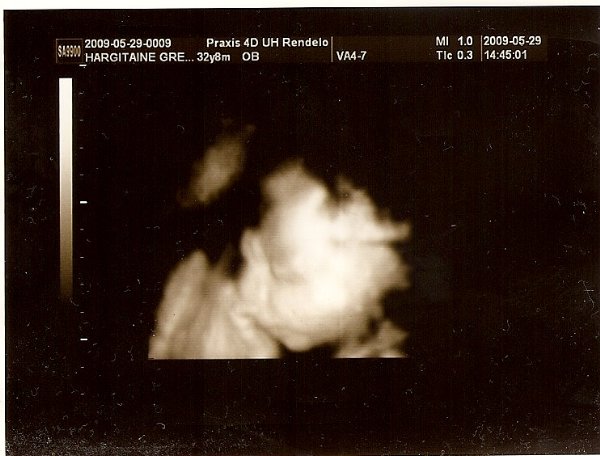

[quote="vicger"][ írta:vicgerimg]https://www.babanet.hu/tarsalgo/attachments/1243880636.351.jpg[/img]

Annyira jó ez a kép szerintem!!!